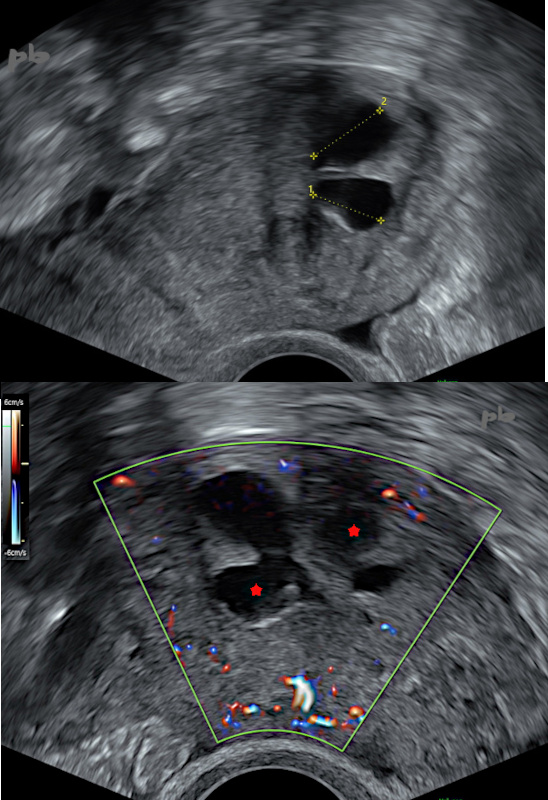

Echographie endovaginale – Coupes de l’utérus, sagittale en haut et transversale en bas.

Les synéchies sont responsables d’un cloisonnement de la cavité utérine, d’où la présence de plusieurs images liquidiennes rétentionnelles plus ou moins communicantes (croix et ★).

L’endomètre qui les borde est fin.